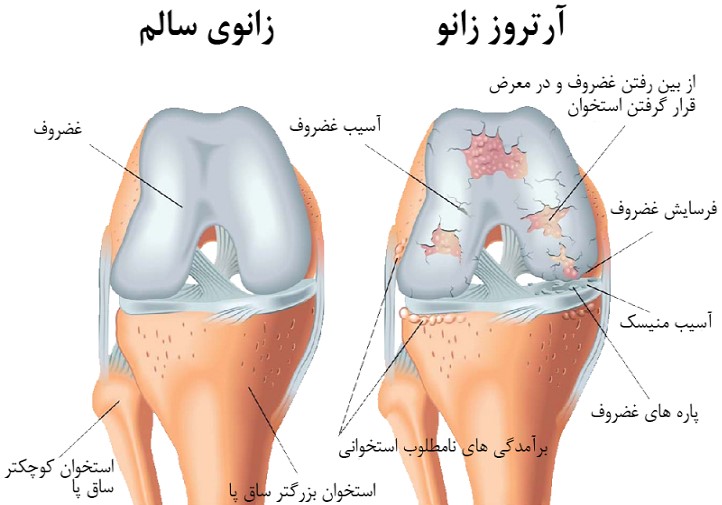

آرتروز زانو بیماری مزمن و پیشرونده مفصلی است که با تخریب تدریجی غضروف و استخوان مفصل، موجب درد، التهاب و کاهش انعطاف پذیری زانو میشود. آرتروز زانو شایعترین بیماری مزمن مفاصل است که در آن غضروف مفصل زانو بتدریج دچار تخریب میشود. ادامه این روند میتواند به ایجاد تغییرات استخوانی منجر شود و علائمی مانند درد زانو، خشکی مفصل و محدودیت حرکت را به دنبال داشته باشد.

آرتروز زانو بیماری مزمن و پیشرونده مفصلی است که با تخریب تدریجی غضروف و استخوان مفصل، موجب درد، التهاب و کاهش انعطاف پذیری زانو میشود. استئوآرتریت زانو بعنوان شایعترین نوع آرتروز، بیشترین تاثیر را بر حرکت و کیفیت زندگی افراد دارد و به دلیل فشار مداوم روی مفصل زانو بیشتر از سایر مفاصل دیده میشود.

مهمترین مشخصه آرتروز، تخریب تدریجی غضروف مفصلی است آرتروز شایعترین بیماری مزمن مفاصل هست زانو بیشتر از مفاصل دیگر به آرتروز مبتلا می شود از علل آن می توان به چاقی، افزایش سن و عوامل ژنتیکی اشاره کرد |

مفصل زانو بزرگترین مفصل بدن است و برای فعالیت هایی مانند راه رفتن، دویدن، پریدن و ایستادن بسیار مهم است. این مفصل پیچیده ای است که از استخوان ها، رباط ها، تاندون ها و غضروف تشکیل شده است که همه با هم کار میکنند تا ثبات و انعطاف پذیری را فراهم کنند. مفصل زانو امکان انجام حرکاتی مانند خم شدن، باز شدن و چرخش را فراهم می کند و آن را برای وظایف و فعالیت های روزمره ضروری می کند. با این حال، همچنین مستعد آسیب و شرایطی مانند آرتروز است. مراقبت از زانو از طریق ورزش زانو، قرارگیری مناسب و استراتژی های پیشگیری از آسیب مهم و حیاتی هست.

– غضروف مفصلی : انت های استخوان ران، درشت نی و کشکک را برای کاهش اصطکاک و جذب ضربه می پوشاند.

– ساییدگی مفصل به مرور زمان منجر به از بین رفتن غضروف مفصل می شود.

علائم آرتروز زانو :

– درد مفاصل، به ویژه با فعالیت یا تحمل وزن

– سفتی و کاهش دامنه حرکتی در زانو

– تورم و التهاب

– صدا دادن مفصل

علائم آرتروز زانو چیست؟

- درد زانو که معمولا به هنگام فعالیت هست ولی با پیشرفت بیماری در استراحت هم وجود خواهد داشت.

- محدودیت عملکرد و درد زانو در راه رفتن و بلند شدن از حالت نشسته و سوار و پیاده شدن از ماشین.

- خشکی مفصل بویژه صبح ها و بعد از نشستن طولانی.

- کاهش دامنه حرکتی مفصل زانو که در مراحل پیشرفته بیماری ایجاد میشود.

- ضعف و لاغری عضلات اطراف مفصل.

- گاهی وجود کریپتاسیون(صدا هایی مانند ترق توروق) در حرکات مفصل زانو.

- گاهی تجمع مایع و ورم زانو در مفصل زانو دیده می شود.

- تغییر شکل در مفصل که در ارتباط با استئوآرتریت زانو بیشتر به صورت پای پرانتزی هست.